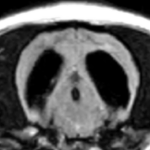

変性性脊髄症と椎間板ヘルニアを併発したウェルシュコーギーの脊髄MRIです。椎間板物質の脊髄への圧迫像がみられます。しかし、MRIだけでは後肢の麻痺がこの椎間板の突出に由来するのか、変性性脊髄症に由来するのかの見分けはつきません。